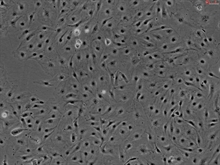

Human Pulmonary Artery Endothelial Cells, Passage 1

The pulmonary artery carries deoxygenated blood from the heart to the lungs. Similar to other vascular endothelial cells, pulmonary artery endothelial cells (PAEC) modulate coagulation and fibrinolysis by producing activators and inhibitors of both processes. In addition, PAEC produce mediators that influence the adhesion and aggregation of blood platelets. PAEC also control vascular tone by synthesizing and processing vasoactive molecules. PAEC further interact with mesenchymal cells and regulate inflammatory events. Such functions of PAEC are implicated in acute lung injury, pulmonary hypertension, edema, embolism, pulmonary artery aneurysm and chronic obstructive lung disease. (SC3100)